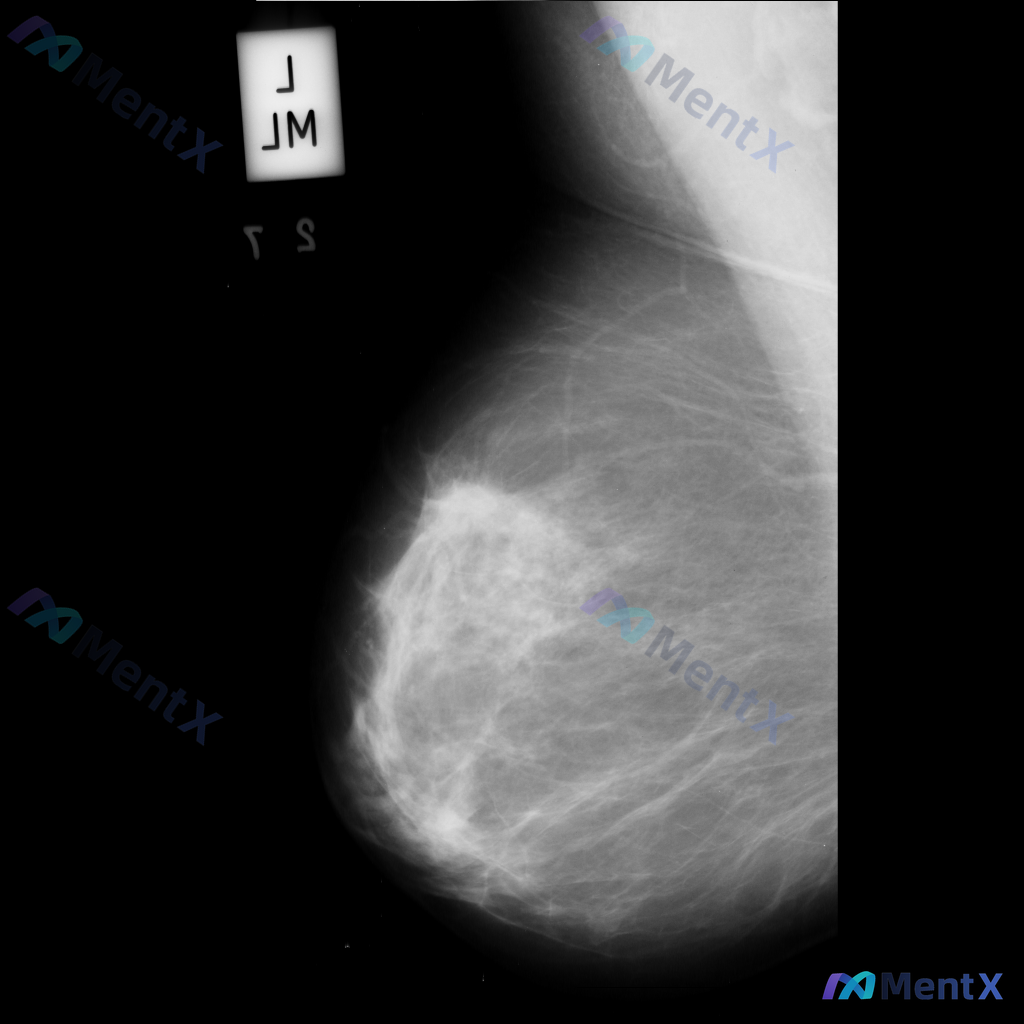

这张左乳钼靶影像,大家看核心异常更倾向哪种情况?

整理到一份乳腺钼靶的影像讨论资料,先和大家同步一下基本信息: - 检查部位:左乳 - 投照体位:内外斜位(MLO) - 影像表现: 1. 左乳外侧偏上象限可见不规则高密度肿块影 2. 肿块边缘模糊,部分区域有毛刺样改变 3. 肿块周围存在局限性结构扭曲 目前先不补充更多信息,想听听大家的第一判断:这...